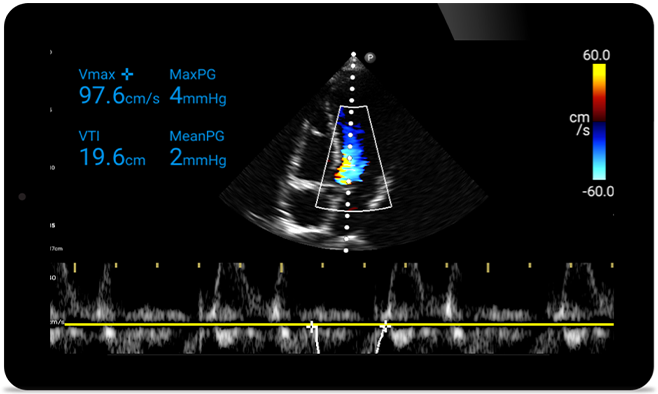

Aja mais rápido para protegero coração do seu paciente

Quando os segundos contam, o ultrassom portátil pode fazer a diferença. O Lumify pode fornecer as imagens de alta definição de que você precisa quando e onde precisar.

Oportunidade de possivelmente reverter a cardiomiopatia

Introdução à ecocardiografia transtorácica